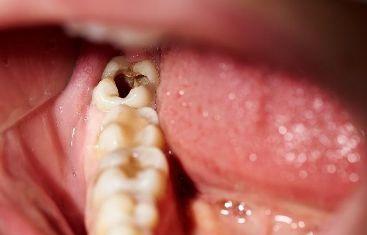

龋齿的临床表现是什么 牙齿由三层硬组织及包绕在其中的软组织构成,硬组织共有三种--牙釉质、牙本质及牙骨质。牙釉质是牙齿的最外层半透明的白色硬组织,钙化程度最高、最坚硬,厚2~2.5毫... 牙齿治疗 鲜清怡 591 2024-02-27

深龋治疗要点是什么 深龋的治疗除了依据龋病的治疗原则之外,必须正确认识深龋对牙髓组织可能产生的影响。深龋对牙本质-牙髓复合体的影响虽然早在釉质龋时,牙髓就开始出现反应,但直到龋损前... 牙齿治疗 阙德厚 553 2024-01-26

深龋的治疗方法有哪些 去净龋坏组织是龋病治疗原则,但应尽量不穿通牙髓,特别是在急性龋时,牙本质脱矿过程进展快,病变组织中细菌侵入相对较浅,去腐质时不必将所有的软化牙本质去净,但洞侧壁... 牙齿治疗 富南烟 665 2023-11-27